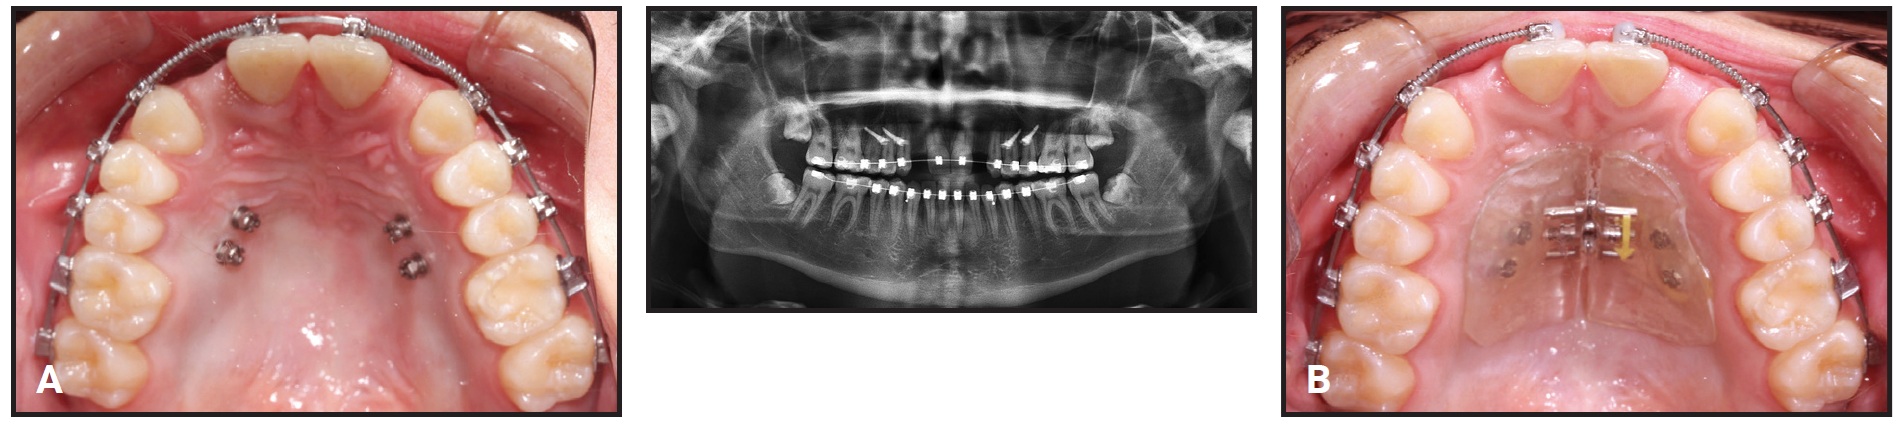

Four palatal mini-implants were placed by a periodontist in the maxillary premolar area, and the MARPE was cemented in place (Fig. 2).

Fig. 2 A. Four palatal mini-implants placed in upper premolar area. B. Expander cemented in place.

Upper and lower .016" × .016" nickel titanium SureSmile archwires were inserted, with open-coil springs in the maxillary lateral incisor spaces. The expander and mini-implants were removed 10 months after placement.